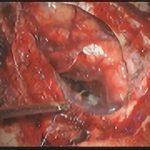

術中写真

摘出 前

摘出 中

摘出 後